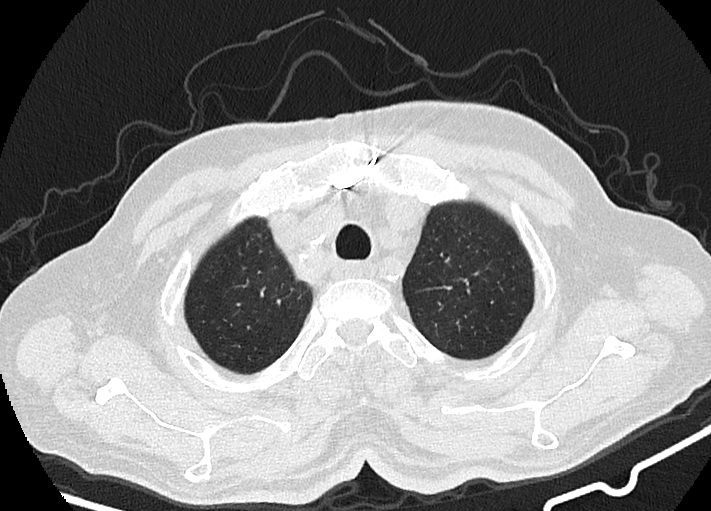

در HRCT از ريه ها(اسپيرال ، مولتي ديتکتور 16، مقاطع اگزيال با ضخامت 1mm بدون فاصله ) ، بدون كنتراست تزريقي :

-Ground glass opacities Patchy پراکنده در ريه ها مشهود است که مطرح کننده Viral pneumonia مي باشد . ( با درگيري 20 درصد حجم ريه )

-کلسیفیکاسیون دیواره آئورت و عروق کرونر ، تغییرات DJD در ستون فقرات ونشانه های CABG مشهود است .

نتیجه: Highly suggestive of COVID-19